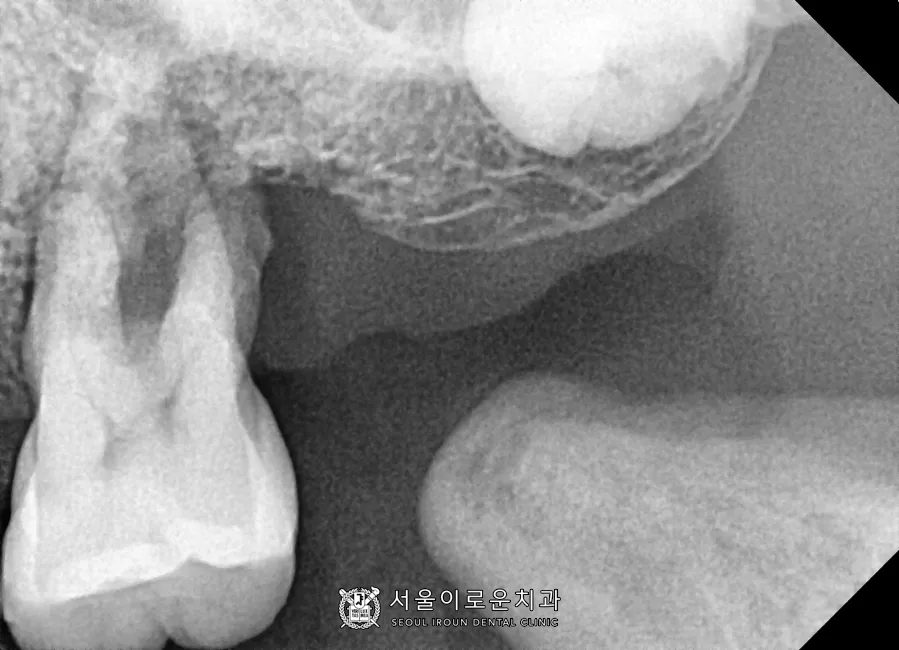

왼쪽 위 어금니(#26) PA 사진입니다.

유일하게 남아있는 큰어금니 (#26)의

상태를 보시면,

1)심한 치주염으로 (→잇몸뼈 소실)

2)2️⃣이상의 동요도(++)와

3) 씹을 때 통증이 있으신 상태로

발치가 필요했습니다.😭